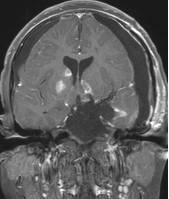

鉴于肿瘤体积超大,而且患儿间断出现意识障碍,直接作手术完全切除肿瘤的难度很大,为降低手术风险,所以我们采用先穿刺肿瘤囊减少肿瘤体积,降低颅压,二期手术争取完全切除肿瘤的策略。行肿瘤囊肿穿刺后,引流出约100多毫升囊液,肿瘤体积显著变小,见图3、图4。

图4.肿瘤囊穿刺手术后肿瘤体积减小

白色箭头示引流管